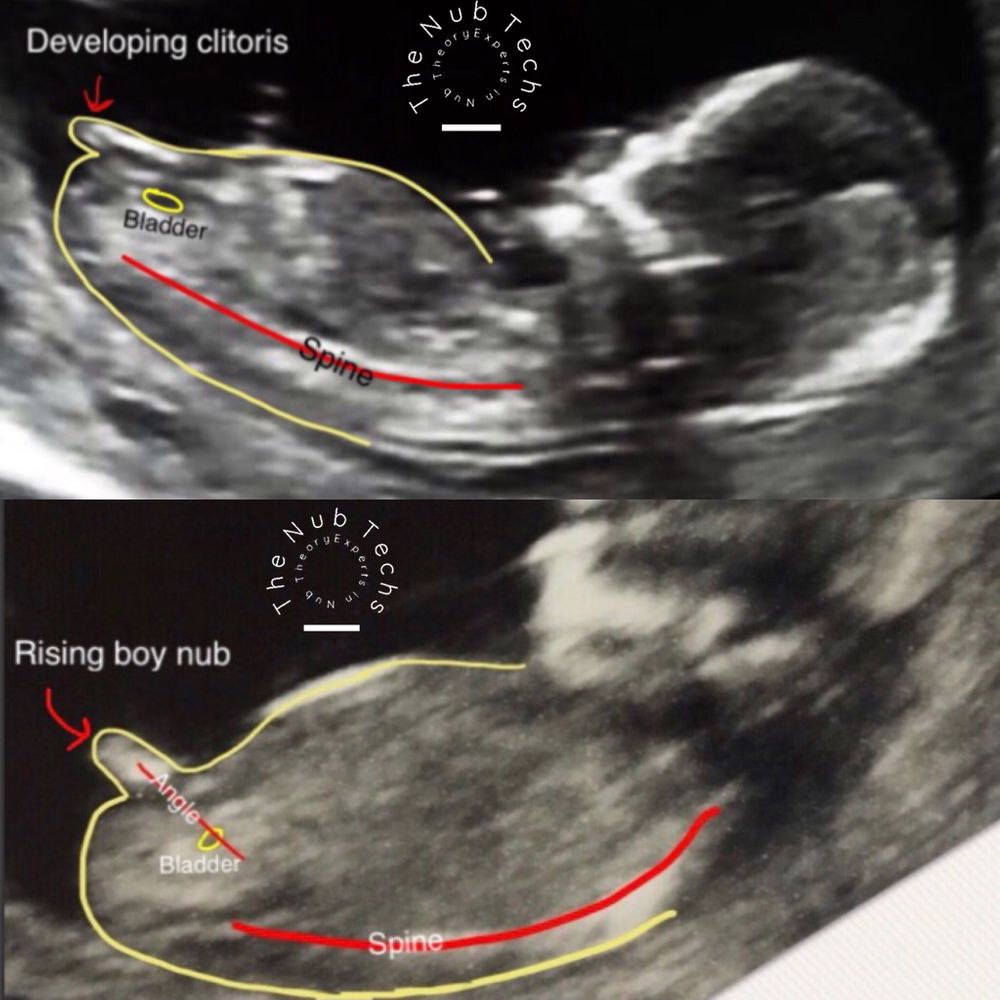

Судя по углу наклона полового бугорка - мальчик) у девочек он более горизонтально расположен

Точно мальчишка) у моего такой же бугорок был в 12,4, слегка вверх Изображение